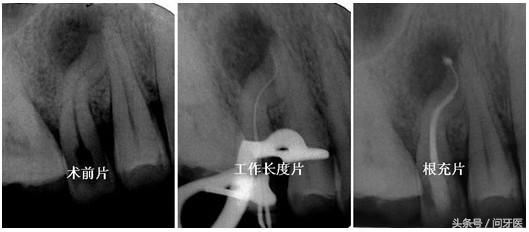

根管治疗过程

根管治疗前后X光片对比